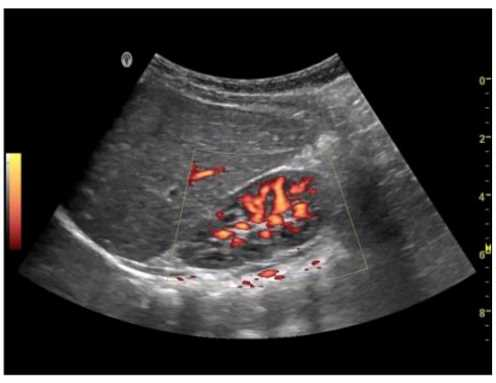

What does this image demonstrate?

1. Presence of flow

2. Direction of flow

3. Color aliasing

4. Color inversion

Answer(s): C

Explanation:

Color aliasing in Doppler ultrasound occurs when the velocity of blood flow exceeds the Nyquist limit, causing the color display to wrap around and display high velocities incorrectly as the opposite direction. This phenomenon is characterized by a mix of colors that indicate flow in both directions at the same location. In the provided image, there is a clear presence of color aliasing, as evidenced by the abrupt color change across the vessel, which is not consistent with normal flow patterns.

Reference:

American Registry for Diagnostic Medical Sonography (ARDMS) Sonography Principles and Instrumentation guidelines.